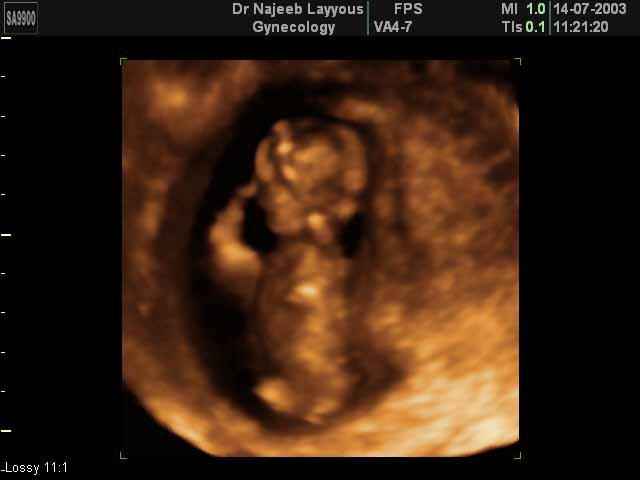

3D First Trimester Ultrasound Scan Photos